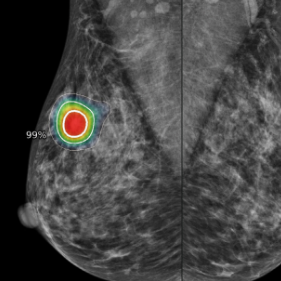

Lunit INSIGHT_deepc